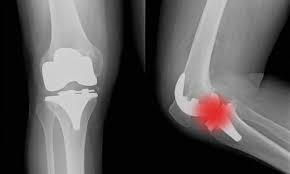

Chirurgia Ortopedica Del Ginocchio Casa Di Cura Rizzola

Artrosi Al Ginocchio Protesi Protocollo Del Dott Nicola Marzano Youtube

Dal Veneto A Mosca Il Modello Di Intervento Di Protesi Al Ginocchio Eccellenza Della Casa Di Cura Rizzola Studiato Da Chirurghi Russi

Ortopedia Ad Alta Complessita Casa Di Cura Rizzola